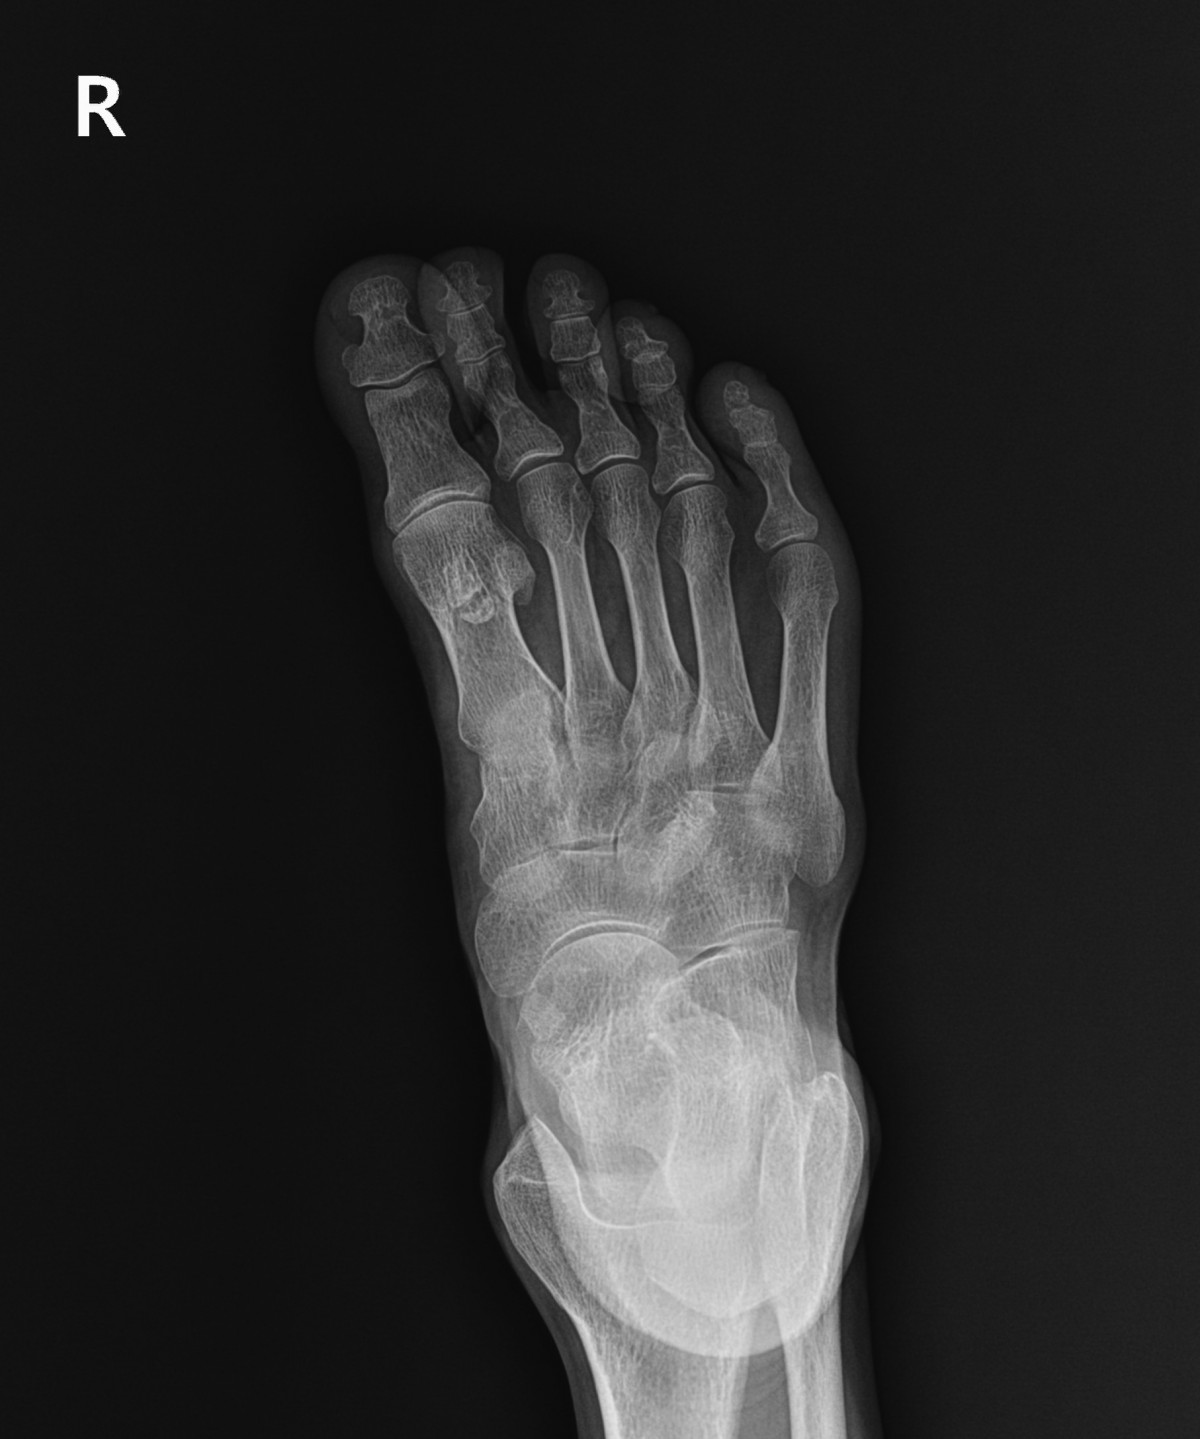

이재상원장님 발가락 골절 수술 김용O 환자

dae765e4d9ac96aee867c9d6292d8784_1758003535_2275.jpg